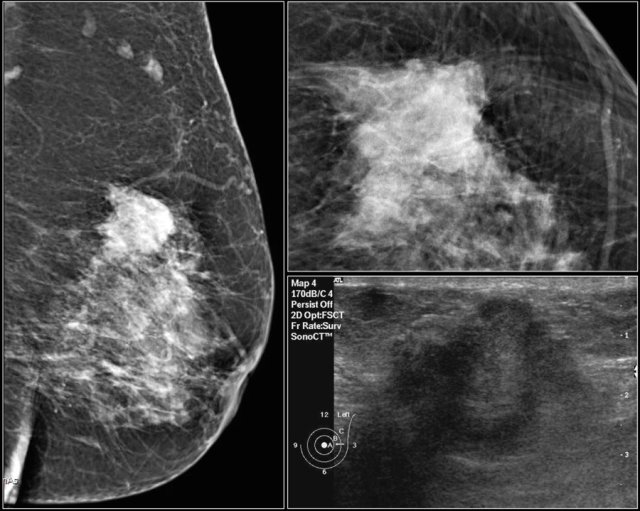

First study the images and describe the findings.

Then continue reading.

The findings are:

- Mass with irregular shape.

- Spiculated margin.

- High density.

- Ultrasound also shows irregular shape with indistinct margin.

This mass is categorized as BI-RADS 5.